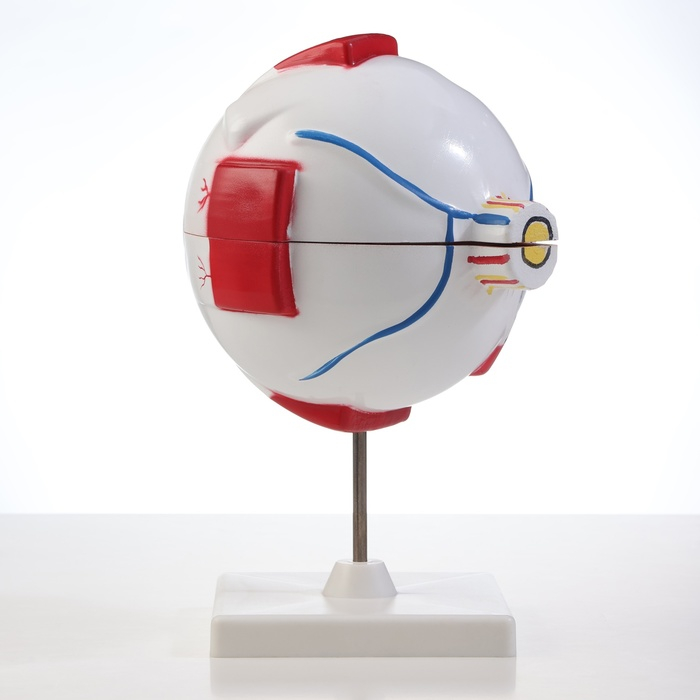

Анатомические модели

ЕКБ 39

No Brand, артикул: 7072361